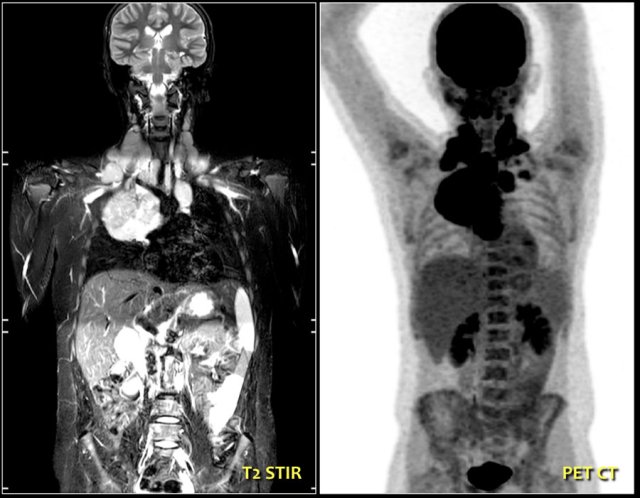

Continue with the MR and PET/CT...

A coronal STIR image shows the pathologic lymph node masses similar to the PET-CT.

The diagnosis was Hodgkin's lymphoma.